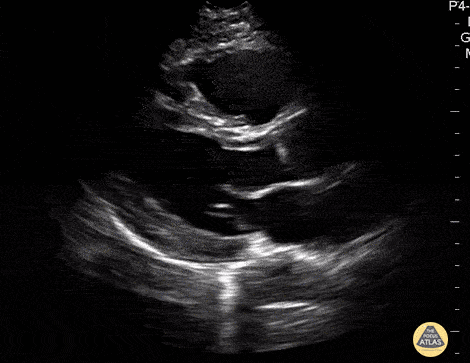

Apical 4 Chamber

• ANATOMIC LANDMARK: apex (5th interspace, ant ax line)

• Probe marker to the right

• SONOGRAPHIC LANDMARK: HEART

• Identify: LV, RV, LA,, RA, MV, TV

• Pericardium +/- Pericardial fluid